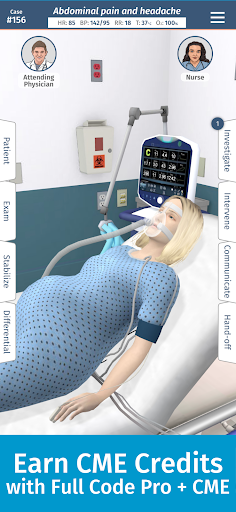

• Full Code Pro + CME cung cấp hơn 100 giờ CME được công nhận

KIẾM TÍN CHỈ CME

Hoàn thành các yêu cầu về giáo dục y khoa liên tục (CME) của bạn với các thử thách mô phỏng linh hoạt và hấp dẫn được công nhận thông qua Hội đồng công nhận giáo dục y khoa liên tục (ACCME). Với đăng ký PRO+CME của chúng tôi, bạn có thể kiếm được tới 100 tín chỉ CME. Đăng ký Full Code Pro+CME để bắt đầu.